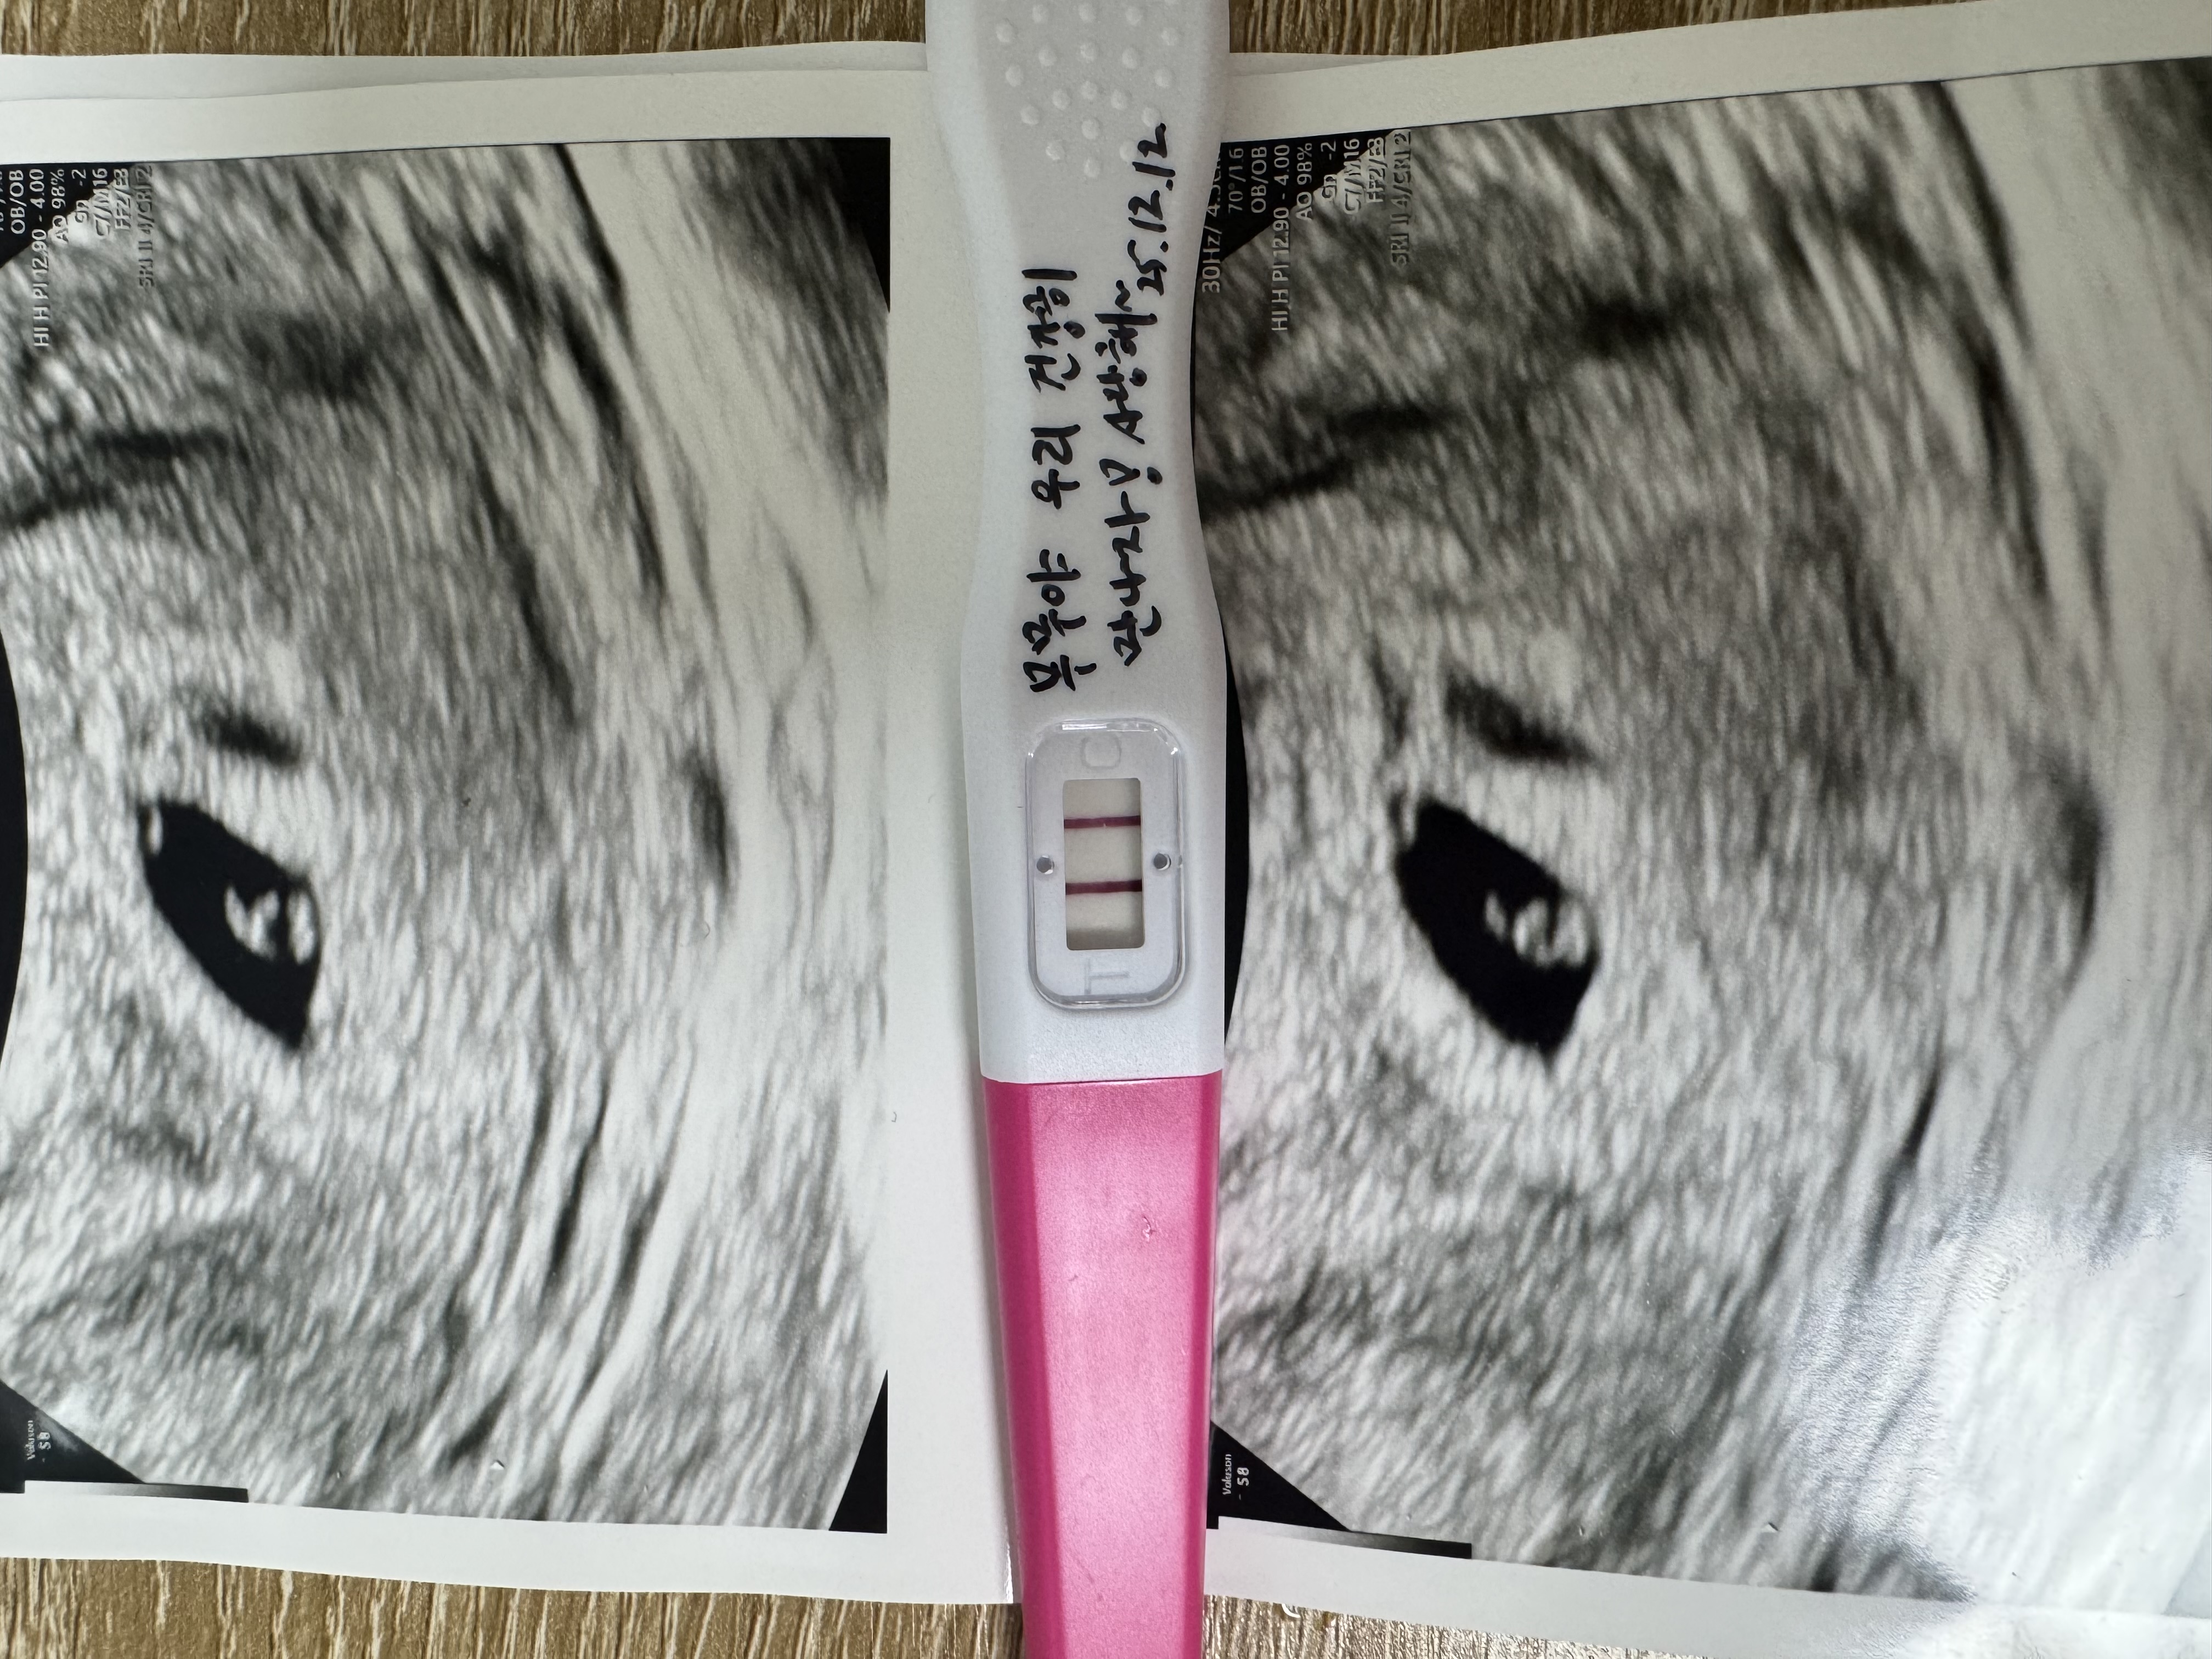

| 가슴 떨리는 임신 이야기를 공유해 주세요. | 시험관 시도 중 매번 실패를 겪으며 이번에도 아닐 거라 생각했습니다. 1차 피검사를 하루 앞두고, 별다른 기대 없이 확인한 테스트기에서 두 줄을 보았을 때 믿기지 않아 한동안 멍해졌던 기억이 납니다. |

| 치료 도중 느꼈던 가장 기뻤던 순간과 절망적인 것들은 무엇인가요? 잊지 못할 경험이 있나요? | 가장 기뻤던 순간은 기대하지 않았던 두 줄을 처음 확인했을 때였습니다. 반대로 시험관 두 번째 시도에서 1차 피검 결과가 0으로 나왔을 때는 큰 절망을 느꼈습니다. 그날의 공기와 감정은 지금도 잊히지 않습니다. |